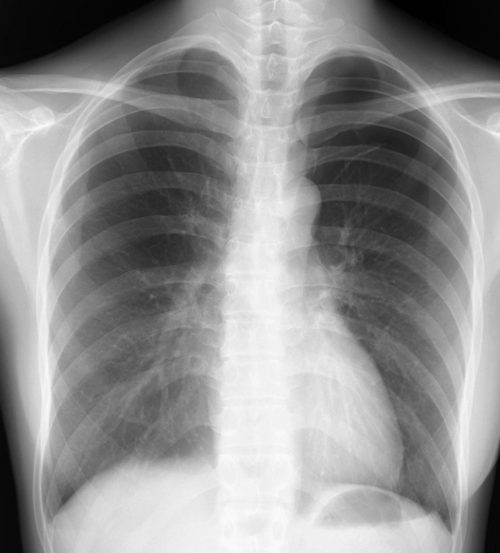

正常像(乳児) ①低年齢(0~3才)は線量、体位、吸気のタイミングが難しいが、比較的よく撮影されている。鎖骨がわずかに不対象、気管の位置が左にずれている。

②線量は適切で黒化度・コントラストとも良好。

③胸郭、横隔膜は正常、胃泡がやや大きい。

④縦隔陰影、頸椎・胸椎陰影は異常をみとめず。

⑤肺門部陰影に問題なく肺野は少し透過性が亢進した印象、左右下肺に肺紋理の増強があるようにみえる。

⑥心陰影は拡大もなく左右辺縁も問題ない。

[評価] 正確な正面像からずれて撮影されている。肺の含気が多く(細気管支炎様)、胃の空気像もやや拡大していて頻呼吸による空気嚥下が考えられる。概ね正常にみえるが、多少の問題点のあるレントゲン像になっている。